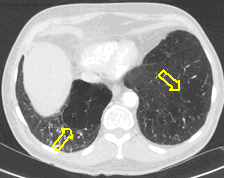

4: Miliary pattern: sarcoidosis, CT, lung window. Axial image and sagittal reformat.

A 67 year old female suffering from COPD. Bilateral rough branching interstitial widening and patchy, miliary nodules with perihilar dominance along the bronchovascular fibres and the fissures.